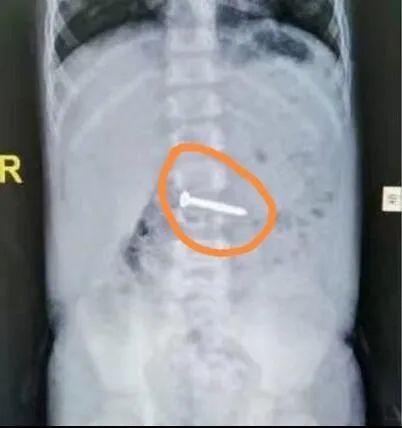

△图中圈住的物品为茂茂误吞的螺丝钉。

抱着胃镜能进到多里面就多里面的想法,钟碧莹将胃镜慢慢往下伸,终于在十二指肠降段处发现了钉子的身影。最后,钟碧莹娴熟顺利地将钉子取出。当她将那枚螺丝钉拿到茂茂妈妈面前时,茂茂妈妈不禁惊呼:“天啊,那么长。”

△茂茂误吞的螺丝钉约有4厘米长。

钟碧莹说:“钉子差点点就进到空肠,这是茂茂第二个不幸中的万幸。”她介绍,茂茂才1岁10个月,肠壁尚未发育完全,而且空肠比较窄,一旦钉子进入空肠,极易出现空肠穿孔,此外,钉子进入空肠后,胃镜无法取出,肠镜也够不到这个地方,只能通过手术取出,而开刀对于这么小的茂茂而言,创伤无疑是巨大的。